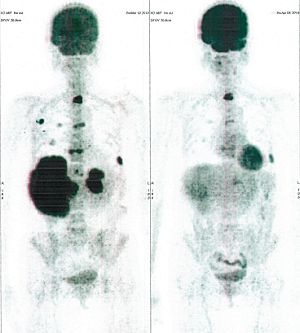

Below are some of the cases, from more than 80 cases we have treated so far with good results. When reading the PET/CT scans, the picture on the left is before treatment, and the picture on the right is after treatment. The intensity of black represents the activity of the cancer, but some black areas are not cancer: brain, heart, radioactive urine in bladder. For the heart, the intensity of black depends on the number of hours of fasting: if more than 10 hours, the heart is not even black, but if fasting is less than 6 hours, it is very black. The intensity of black in the brain can be variable in different scans depending on the brain activity at the time of the scan. The intensity of black in the radioactive urine can also be variable due to the hydration of patients and the time of injection of diuretic.

CASE NO: 1

(HEPATOCELLULAR CARCINOMA + STOMACH CANCER)

A middle-aged women who is very thin and very weak, can hardly walk, lying in bed most of the time. She saw a cancer specialist in a top hospital who discovered that she had massive hepatocellular carcinoma, and another cancer in the stomach. Given that hepatocellular carcinoma is incurable and stomach cancer is very difficult if not impossible to cure without surgery, she was told that nothing could be done for her. She came to ask us to help her. After just 4 treatment, the hepatocellular carcinoma went into remission, and the stomach cancer (arrow) became less active. Until today, more than 6 months later, the hepatocellular carcinoma is still in remission.